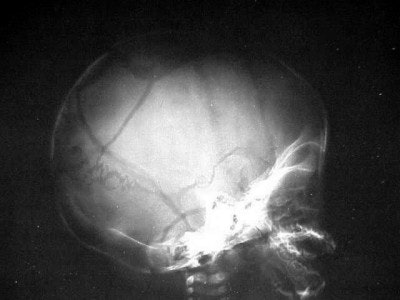

In some cases of non-accidental trauma (formerly called child abuse) we see infants with skull fractures. These eggshell fractures (figures 9 and 10) are consistent with the child’s being held by his ankles and swung against an inanimate object, in this case, a coffee table.

![]() |

| Figure 9 |

| Figure 10 |